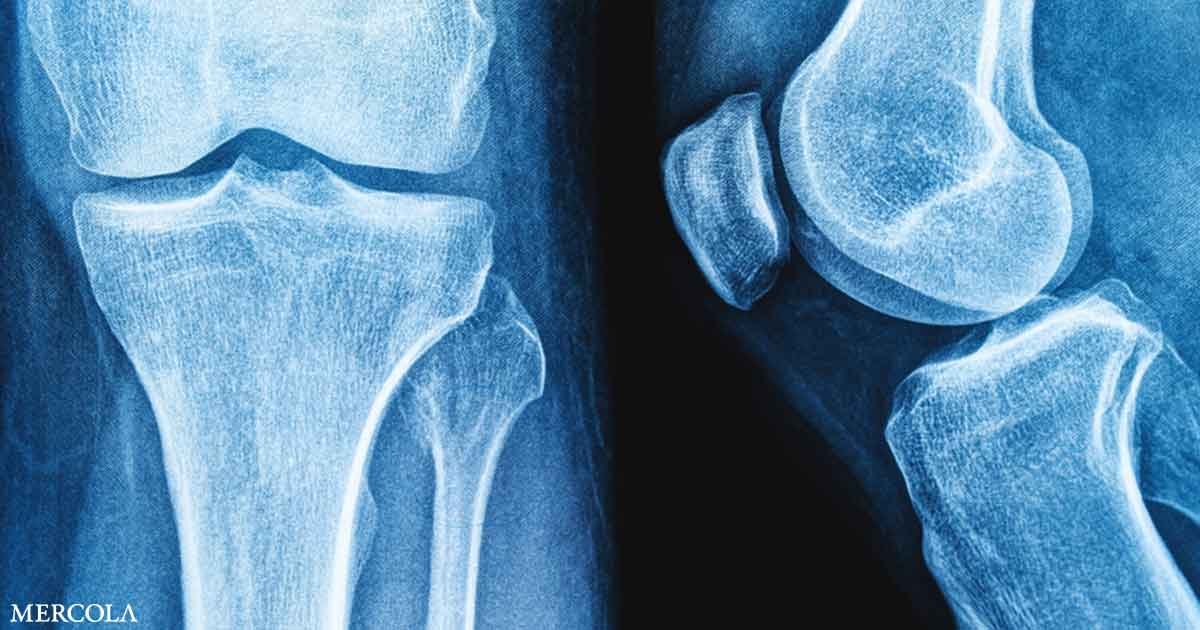

Home Health and LifestyleMicroplastics Could Be Weakening Your Bones, New Study Finds

Microplastics Could Be Weakening Your Bones, New Study Finds